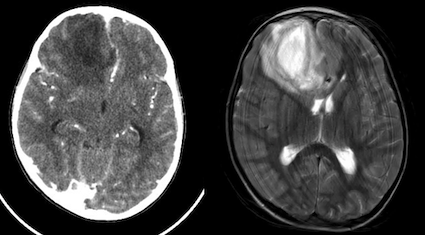

Bambino di 9 anni che viene portato in Pronto Soccorso per persistenza di febbre che dura da circa una settimana, associata a cefalea e vomito che sono comparsi nelle ultime ore. È in terapia da alcuni giorni con amoxicillina per una sinusite. Obiettivamente il bambino preoccupa, è molto pallido, risponde a tono alle domande, ma tende ad assopirsi, complessivamente il suo GCS è di 14. All’esame obiettivo neurologico il test di Lasegue è negativo e, pur non avendo un franco rigor del collo, il bambino lamenta dolore alla flessione. Eseguiamo immediatamente una dose di ceftriaxone nel dubbio di una meningite. Gli esami ematici sono subito indicativi per un’infezione con una spiccata leucocitosi neutrofila e indici di flogosi elevati. Alla luce del quadro clinico, associato a una tendenza alla bradicardia (FC 55-65 bpm), pur senza ipertensione, decidiamo di eseguire un esame neuro radiologico urgente per escludere una lesione intracranica: la TC ci mostra che il bambino ha un ascesso cerebrale frontale destro con edema limitrofo e iniziale shift della linea mediana (Figura 1). A questo punto vengono somministrati metronidazolo, desametasone e mannitolo. Il bambino viene trasferito in Neurochirurgia dove viene eseguita una RM che conferma il quadro visto in TC; viene quindi aggiunta alla terapia antibiotica la vancomicina e viene eseguito il drenaggio dell’ascesso. Alla luce delle difficoltà di svuotamento completo della lesione il bambino viene quindi trasferito in un Centro neurochirurgico pediatrico dove l’esecuzione di un ulteriore drenaggio, associato a una variazione della terapia antibiotica con cefotaxime, cotrimossazolo e clindamicina, portano a un progressivo miglioramento del quadro.

In questo caso clinico ci troviamo di fronte a uno dei meccanismi più tipici di formazione di un ascesso cerebrale; l’infezione si è infatti propagata da un focolaio di infezione contiguo (25-50% dei casi di ascesso cerebrale), una sinusite. La stessa complicanza può accadere nell’otite media/mastoidite o in un’infezione odontogena. Gli altri meccanismi patogenetici sono la diffusione ematogena e l’inoculazione diretta (es. corpo estraneo). I sintomi (vomito, cefalea e bradicardia) sono suggestivi per un’ipertensione endocranica. Frequente il riscontro obiettivo di meningismo. L’imaging urgente (RM se possibile, TC in alternativa) gioca un ruolo fondamentale nella diagnosi differenziale e il riscontro della tipica lesione cercinata è sempre diagnostico. Da evitare nel percorso diagnostico la puntura lombare per il rischio di erniazione cerebrale, considerando che l’analisi del liquor non aggiunge informazioni utili alla gestione o al trattamento.